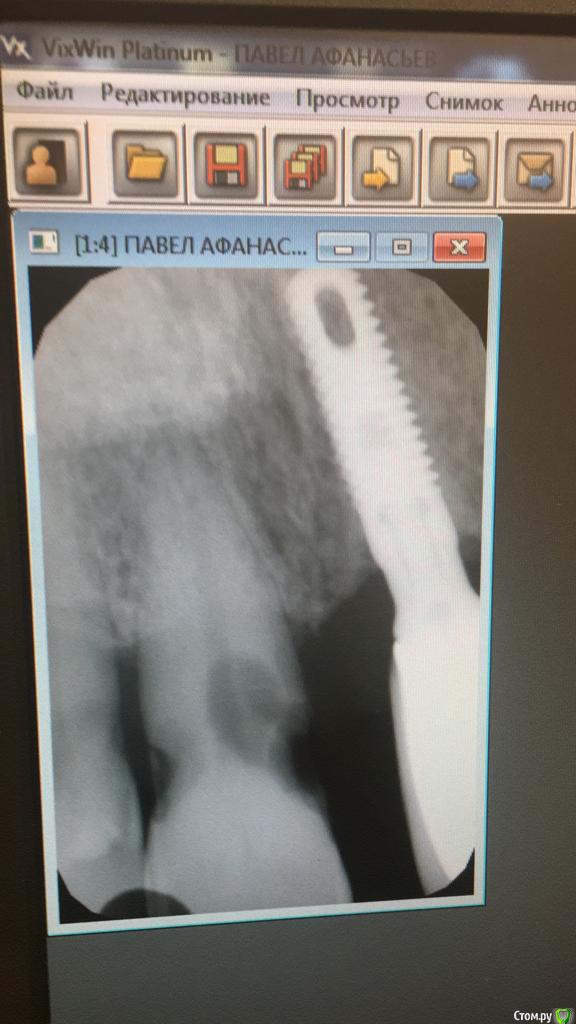

rytovst Опубликовано 27 сентября, 2018 Поделиться Опубликовано 27 сентября, 2018 Подскажите, что за система Ссылка на комментарий

АнтонТЛТ Опубликовано 27 сентября, 2018 Поделиться Опубликовано 27 сентября, 2018 Подожди на Zimmer Tapered Screw-Vent 1 Ссылка на комментарий

ivanov6988 Опубликовано 29 сентября, 2018 Поделиться Опубликовано 29 сентября, 2018 Зиммер тсвт. Платформа как у израиля. На постоянном абатменте 1* конус Ссылка на комментарий

rytovst Опубликовано 8 октября, 2018 Автор Поделиться Опубликовано 8 октября, 2018 (изменено) Zimmer Tapered Screw-Vent именно они Спасибо ! Изменено 8 октября, 2018 пользователем rytovst Ссылка на комментарий